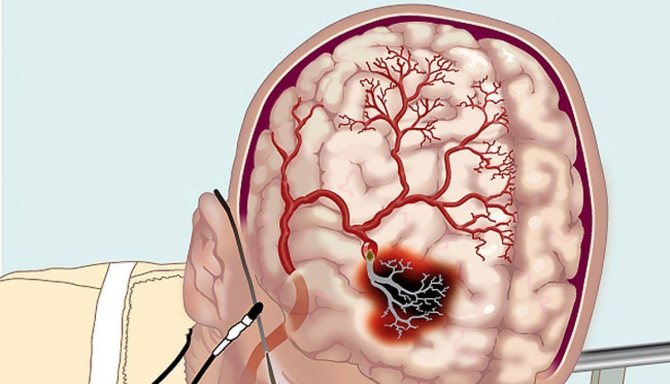

ОНМК вне зависимости от своего типа является терапевтической патологией, которая имеет под собой органический субстрат. Говоря более доступным языком, инсульт – это заболевание, при котором патогенетические механизмы формируют очаг некроза в коре головного мозга (будет дальше по тексту упоминаться как ГМ) или же в подкорковых структурах. Соответственно, это будет органическое поражение, а вся наличествующая клиника определяется его размерами и местом дислокации.

Нейрохирургические операции (имеются в виду вмешательства на ГМ) проводятся как при ишемических ОНМК, так и при геморрагических. При манифестации кровоизлияний в мозг зачастую возникают инсульт-гематомы, а также не исключено возникновение спонтанного субарахноидального кровоизлияния, обусловленного разрывом аневризмы. Этот термин подразумевает мешотчатую деформацию сосуда – увеличивается многократно его диаметр за счет истончения стенки. Имееющее глубинную локализациюкровоизлияние во многих случаях ассоциировано с прорывом крови в систему желудочков ГМ. В свою очередь, этот патофизиологический механизм приводит к нарушению ликвороциркуляции и появлению так называемой гидроцефалии окклюзионной этиологии. Основными целями, которые преследует хирургическое лечение, принято считать следующие:

Оперативное вмешательство при геморрагических инсультах, как правило, выполняется при кровоизлияниях в ГМ, из которых впоследствии развиваются инсульт-гематомы. Подобного рода проблема возникает после разрыва аневризмы. Кровоизлияния, в частности, глубинные приводят к тому, что кровь разливается в систему желудочков ГМ. В том случае, если операция не будет проведена в кратчайшие сроки, подобного рода состояние станет причиной манифеста так называемой окклюзионной гидроцефалии — частичной обтурации или тотальной блокаде одного-двух отверстий, расположенных между желудочками.

Главной причиной развития инсульта является острое нарушение кровотока в одной из частей мозга из-за перекрытия или разрыва сосуда. Способствовать этому опасному для жизни состоянию может как ряд определенных факторов, так и обширный перечень болезней, приобретающих со временем хронический и запущенный характер.